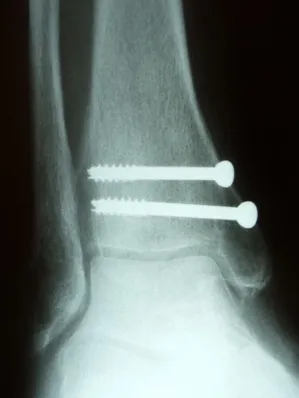

Pics status post percutaneous repair with 2 screws